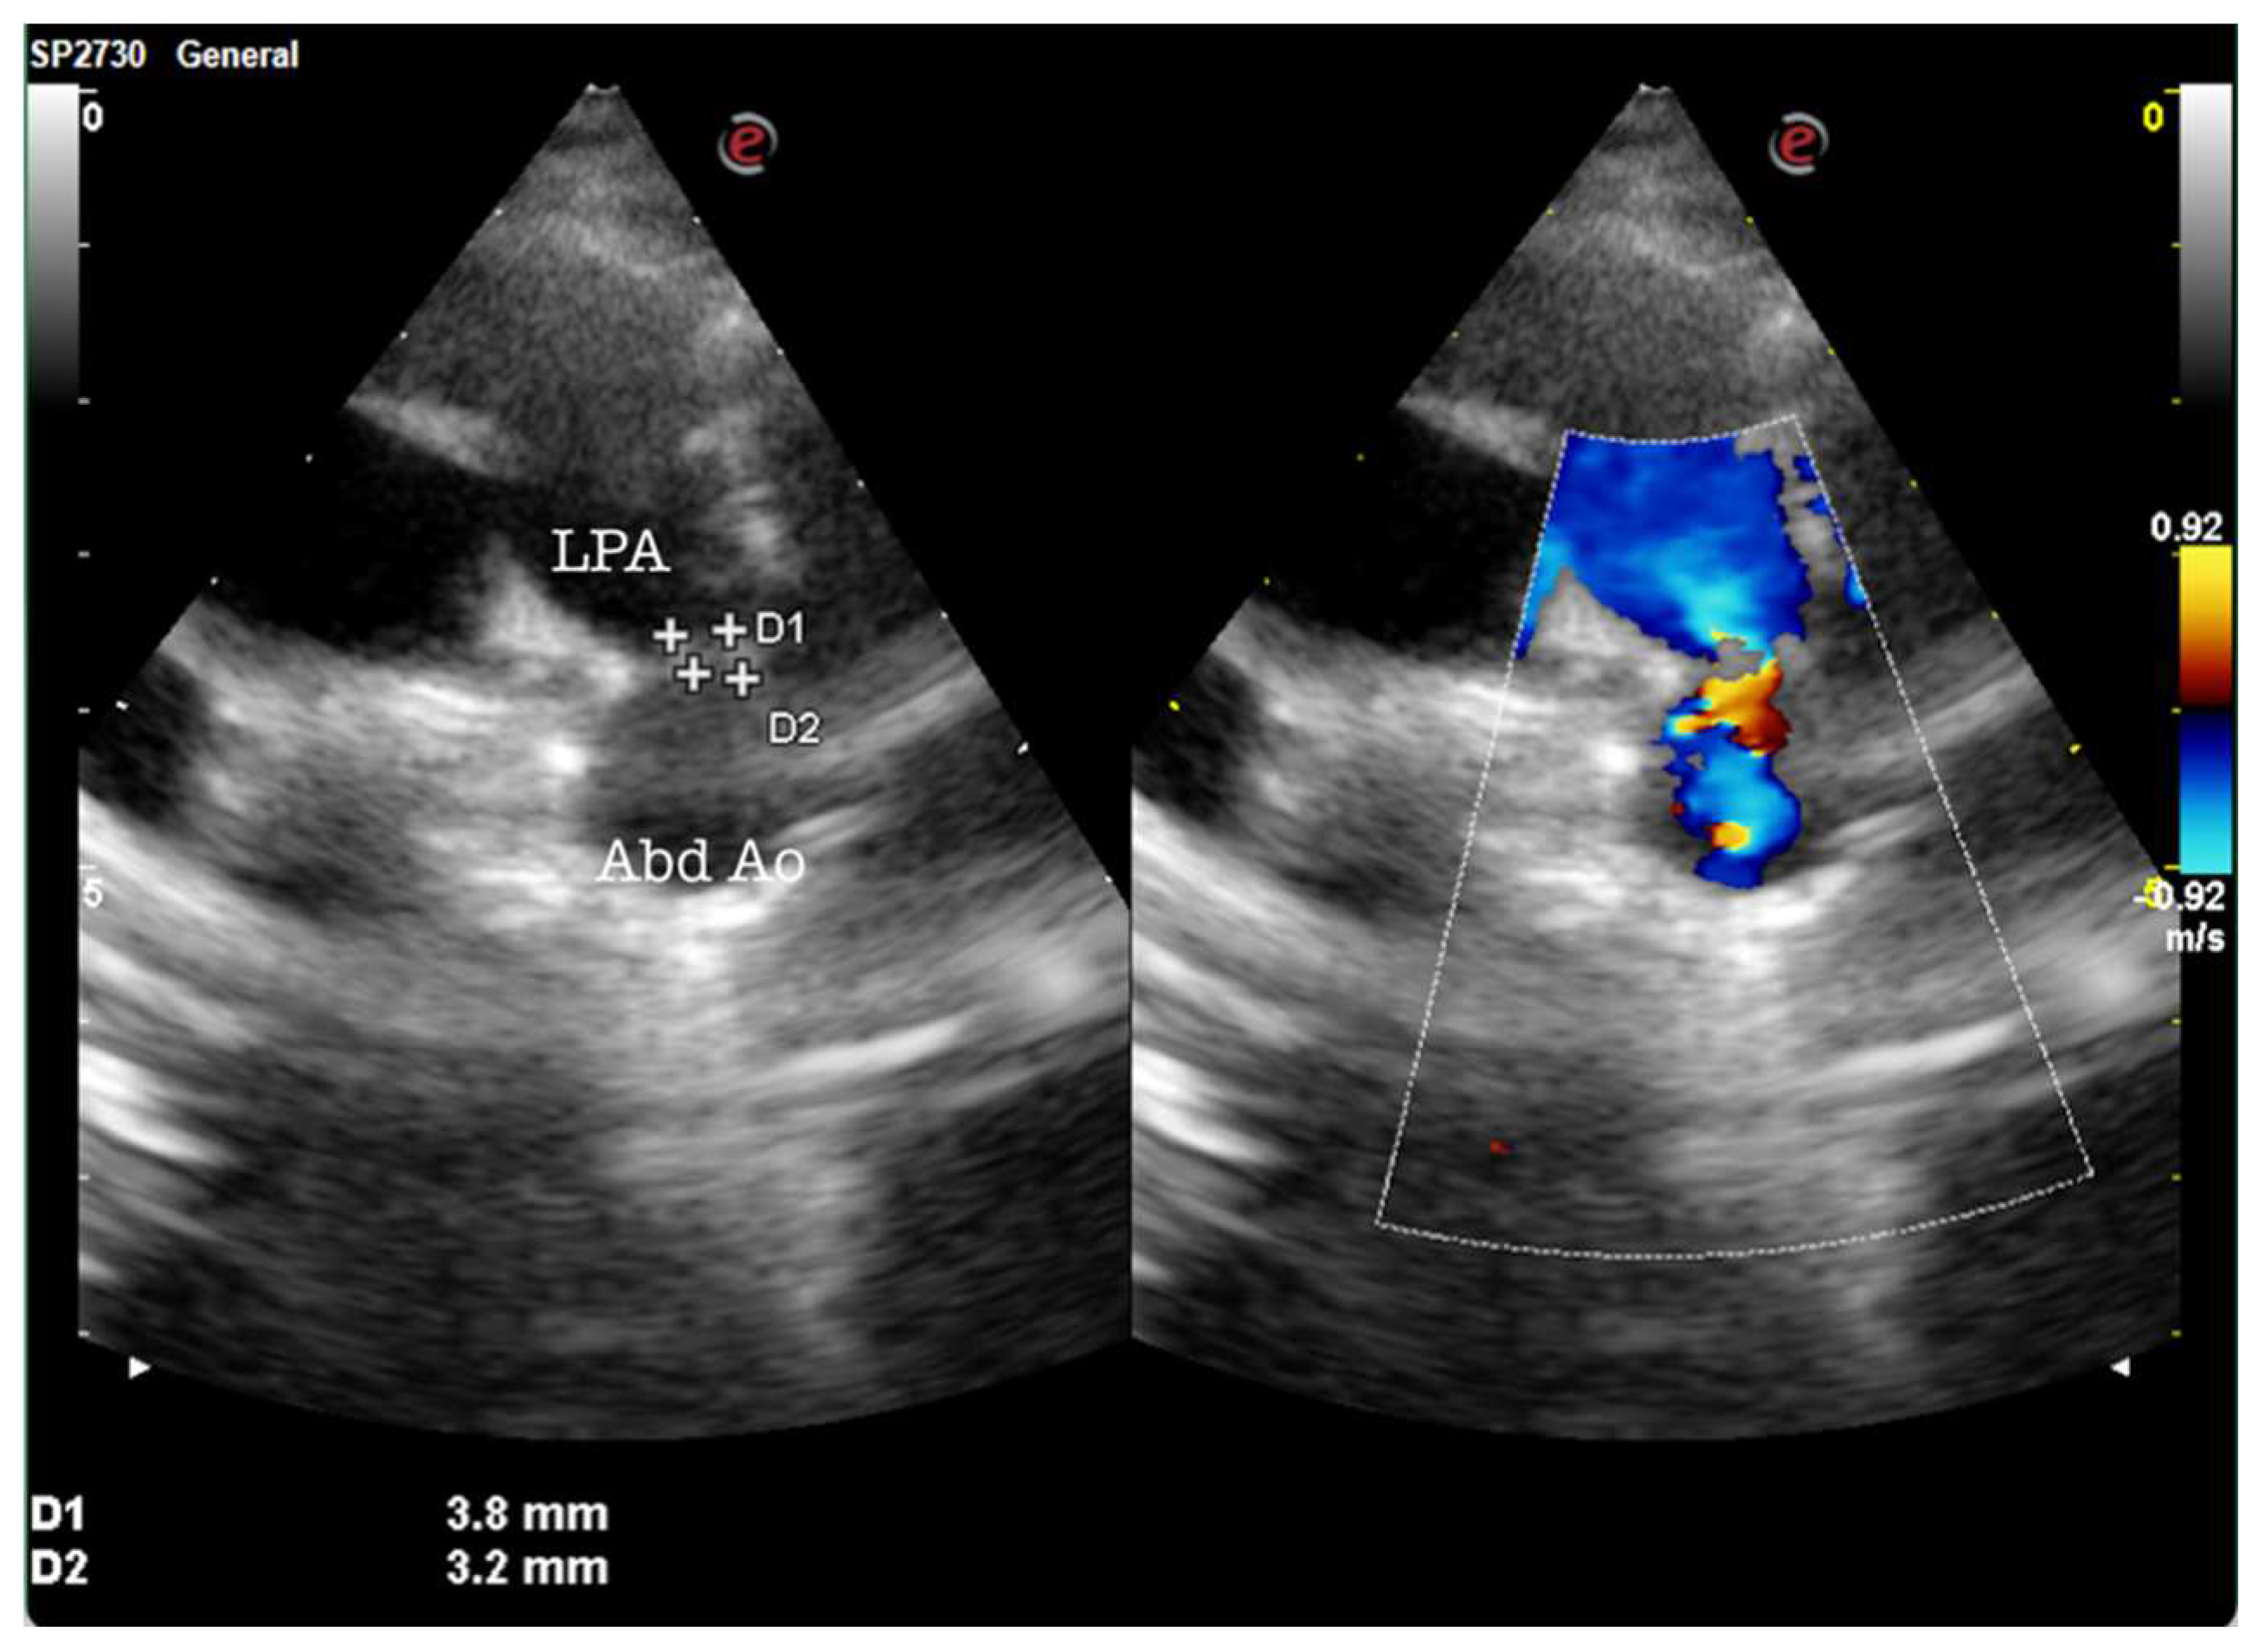

During the admission and care of these newborns, a multidisciplinary team performed ultrasonographic examinations all of the readmitted newborns, especially preterms and IUGR newborns. Of those evaluations, 12 underwent abdominal ultrasound, 19 required cerebral ultrasonography, and 15 required heart ultrasounds. What was interesting was the fact that two of them were diagnosed in the pediatric unit with patent ductus arteriosus, as observed in Figure 2.

Figure 2. Patent ductus arteriosus (PDA): modified parasternal view showing a moderate tubular/conic patent ductus arteriosus (red flow). LPA - left pulmonary artery; Abd Ao - abdominal aorta.